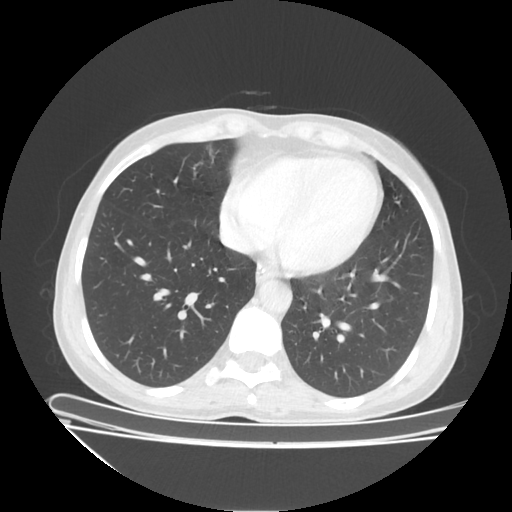

Original NATIVE CT scan (input)

Mediastinum window (WL 40, WW 400 β†’ Low βˆ’160, High +240)

Reconstructed NATIVE CT scan (cycle consistency)

Original VENOUS CT scan

Generated VENOUS CT scan (A→B translation)